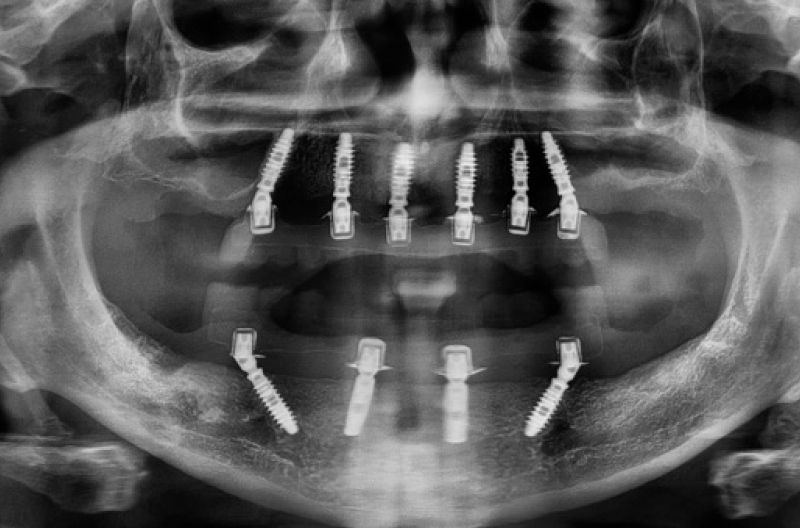

Dopo 4 mesi ho rivisto il paziente per la realizzazione della Toronto conometrica provvisoria nellŌĆÖarcata superiore (Figg. 26-29).

Fig. 26 – OPT a 4 mesi dallŌĆÖintervento

Fig. 60 – OPT post consegna. Le cappette Fixed in PEEK sono radiotrasparenti